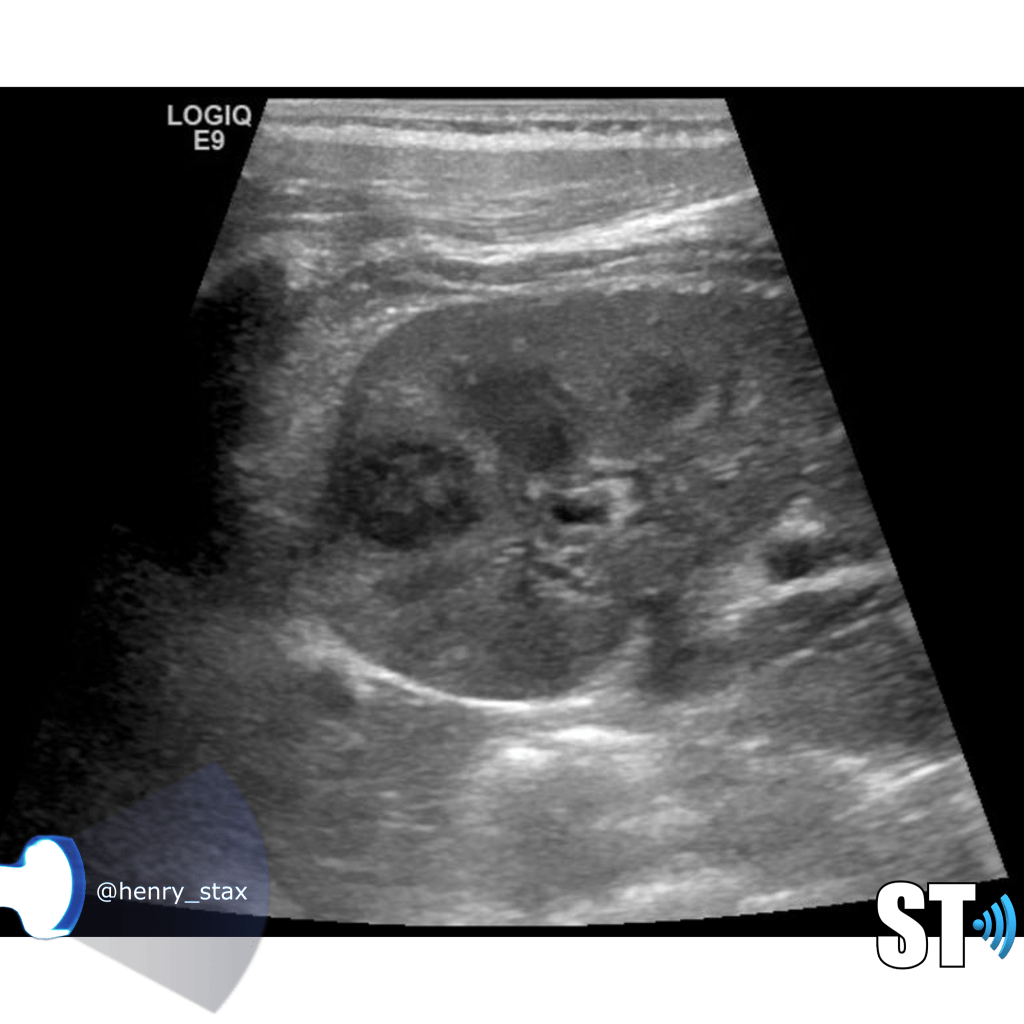

Renal Cystic Disease

Renal cysts are very common and as a sonographer you’ll encounter them frequently in the pediatric and adult populations. Approximately 50% of people who are 50 years and older have simple kidney cysts. The majority of parenchymal cystic lesions are simple epithelial cysts. They have thin walls, are anechoic, good through transmission. They can have thin septations or internal debris(5%) these may require follow up. Chronically some can develop calcifications on their walls.

Simple cysts

Cysts are non functioning parts of the kidney. Simple cysts typically pose no health problems. Simple cysts are often found incidentally when the patient is undergoing a procedure for some other complaint. To meet the criteria for cysts the lesion should be

- Round or oval

- Thin wall

- Anechoic

- Good through transmission (posterior acoustic enhancement)

MCDK

Multicystic Dysplastic Kidney results from a ureteral obstruction before the 8th or 9th week of fetal development. MCDK is usually diagnosed prenatally or shortly after birth if an ultrasound is ordered. The affected kidney is non functioning and is replaced by cysts of various sizes and connective tissue.

- Malformation of the kidney during fetal development

- Multiple cysts

- Contralateral UPJ obstruction is found in 3% to 12%

- Usually unilateral (bilateral form is usually fatal)